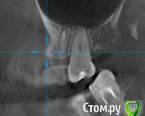

St. Опубликовано 26 августа, 2016 Поделиться Опубликовано 26 августа, 2016 Все три пролечены не очень хорошо, в идеале перелечить и сделать на них коронки. Но на сладкое ни один из них не может реагировать. Возможно реагирует 7 или 3, у которых оголена часть корней за счет вашего парадонтита. 1 Ссылка на комментарий

Гарриевич Опубликовано 27 августа, 2016 Поделиться Опубликовано 27 августа, 2016 возможно пропущенный канал, а возможно Вам "кажется" и реагируют все таки живые зубы. В любом случае данный снимок показывает не очень качественное лечение, но это только снимок 1 Ссылка на комментарий

татьяна tat Опубликовано 27 августа, 2016 Автор Поделиться Опубликовано 27 августа, 2016 возможно пропущенный канал, а возможно Вам "кажется" и реагируют все таки живые зубы. В любом случае данный снимок показывает не очень качественное лечение, но это только снимок Ссылка на комментарий

Beznika Опубликовано 8 сентября, 2016 Поделиться Опубликовано 8 сентября, 2016 на 5 ке материал вывели за апекс. резекцию возможно придётся делать верхушки корня... + карман у вас есть за 6кой. а так всё равно перелечивать надо... масса пористая в каналах и не гомогенная. (не однородная) Ссылка на комментарий